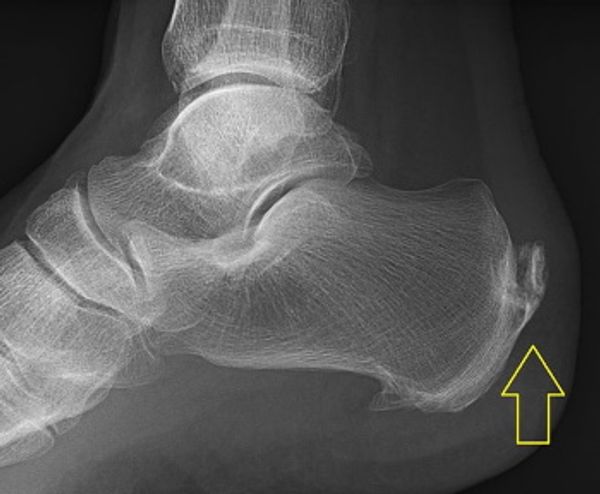

Leestijd: 5 minutenHet is een pijnlijke aandoening, waar relatief veel mensen tussen de 40 en de 60 jaar last van hebben; we hebben het hier over hielspoor, over pijn onder het bot van de hiel bij het staan en lopen. De pijn lijkt op pijn die gevoeld wordt als je een steentje in je schoen hebt. Eigenlijk is hielspoor als naam voor een aandoening niet helemaal juist. Een hielspoor is namelijk een extra stukje bot of verkalking bij de aanhechting van de hielpees aan het hielbeen (het calcaneus). Uit onderzoek blijkt dat 75% van alle volwassenen zo’n extra stukje bot, dat ook spina calcaneï wordt genoemd, heeft en dat dit lang niet altijd tot klachten leidt. Waarschijnlijk ontstaan de pijnklachten door het langdurig drukken van dit botje op de pees in de hiel, die hierdoor kan gaan ontsteken. Voel je pijn aan de zijkant van de hiel, dan hebben de klachten niets met hielspoor te maken; dan is er iets anders met de voet aan de hand.